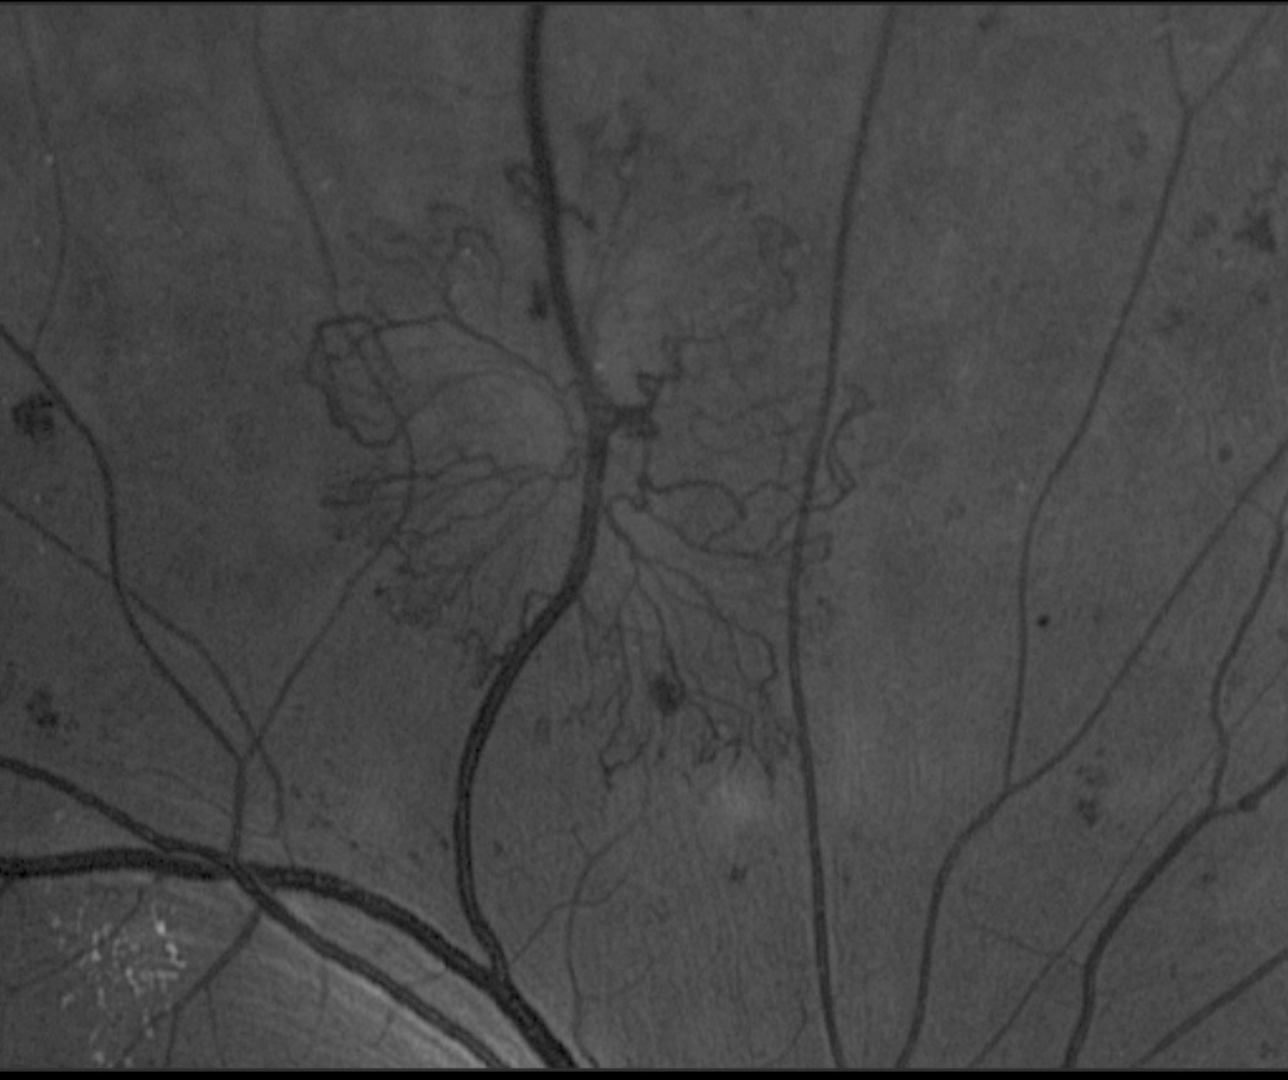

Case 1: Neovascularisation Elsewhere (sea-fan formation)

A 34-year-old female with type 1 diabetes, diagnosed when she was 17 years old. She reports a history of poor glycaemic control that has been progressively improving in recent years. Her most recent HbA1c was 8.1% and she reports no numbness or tingling in her extremities. Her best corrected visual acuity in the left eye is 6/9.5 (20/30). This case will focus on the left eye only.